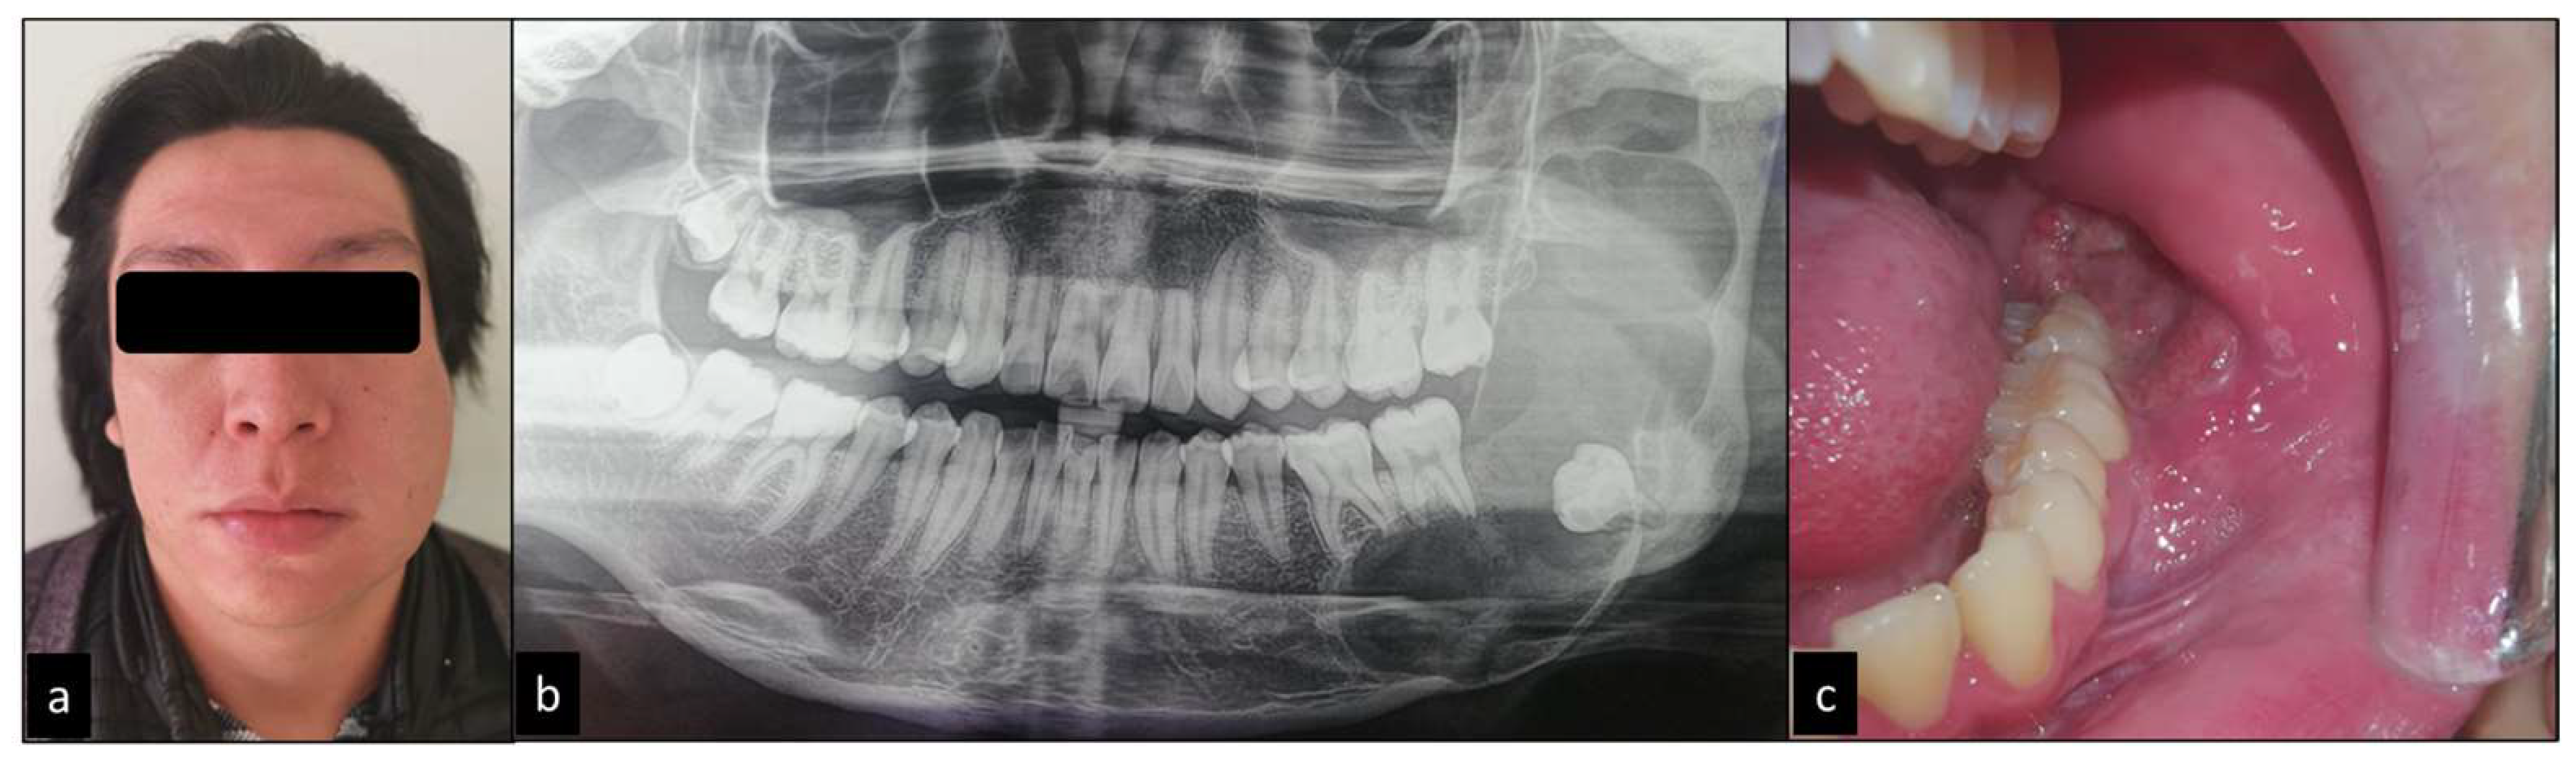

Conservative treatment of ameloblastoma in mandible case report Issuu Ameloblastoma Hereditary Ameloblastomas grow from the same type. Web ameloblastoma is characterized by an abnormal growth in the sinus area or jaw, often at the site of the third molar. Ameloblastomas represent about 1% of all jaw. Web ameloblastomas are benign but locally invasive neoplasms which may grow to massive proportions and cause significant. Web ameloblastomas are benign but locally invasive neoplasms. Ameloblastoma Hereditary.

Ameloblastoma in a pediatric patient Characteristics, treatment and Ameloblastoma Hereditary Web ameloblastoma is characterized by an abnormal growth in the sinus area or jaw, often at the site of the third molar. Ameloblastomas represent about 1% of all jaw. Web ameloblastoma is a rare kind of tumor that starts in your jaw, often near your wisdom teeth or molars. Web ameloblastomas are benign but locally invasive neoplasms which may grow. Ameloblastoma Hereditary.